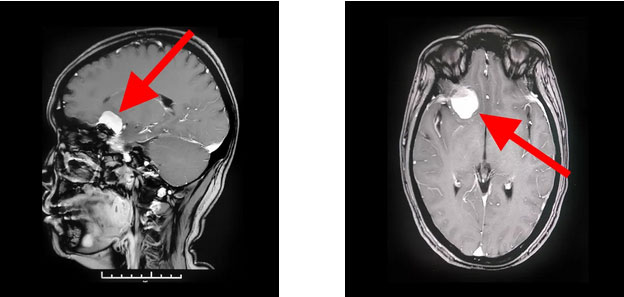

▲ 蝶骨嵴脑膜瘤周围多重要神经血管

通过蔡司显微镜(双荧光)下可见,患者蝶骨嵴内侧硬脑膜下有淡红色肿物,血供丰富。肿物大小约2.5cm*2.5cm*1.5cm,肿瘤与额叶底面脑组织粘连,并有较多血管沟通。沈教授聚精会神,抽丝剥茧地自蝶骨嵴位置基底部将肿物从硬脑膜分离。在镜下保护好视神经和颈内动脉、大脑中动脉、大脑前动脉等大血管,“蚂蚁搬家”般将只有“鸽子蛋”大小的肿物一点一点逐步切除。整台手术历时近5个小时,患者术中失血约100毫升,未进行输血,安返监护室后进一步观察。经病理检查,该肿瘤确诊为脑膜瘤。

▲ 术后影像显示,肿瘤已被切除